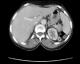

La maladie de Kaposi est une maladie angioproliferative multifocale, dont les localisations cutanéo-muqueuses sont les plus fréquentes. Nous en rapportons un cas avec une atteinte musculo squelettique. Patiente de 55 ans, présente depuis un an de multiples nodules angiomateux confluents en des tumeurs ulcéro bourgeonnantes sur un placard hyperpigmenté et oedème de la jambe gauche, associés à des macules angiomateuses de la plante du pied droit. La biopsie cutanée était en faveur d'une maladie de kaposi, la sérologie VIH était négative. Le bilan lésionnel objectivait une lyse du premier et du deuxième métatarsien, des micronodules parenchymateux pulmonaires bilatéraux, des adénopathies pré trachéales, et une lésion musculaire para vertébrale de 3 cm prenant fortement le contraste (figure 1). L'atteinte du système musculo-squelettique dans la maladie de Kaposi est très rare, seulement 66 cas publiés dans la littérature, dont 3 uniquement comprenaient une atteinte musculaire, avec une sérologie VIH positive. Les lésions osseuses étaient les plus fréquentes. Les patients étaient rarement asymptomatiques, presque tous les patients avaient des lésions concomitantes non osseuses. Chez notre patiente, il s'agit d'une maladie de Kaposi classique avec une atteinte multifocale: cutanée, pulmonaire, ganglionnaire, osseuse par contigüité et musculaire para vertébrale sans atteinte cutanée en regard, ce qui fait la particularité de notre observation. Un traitement à base d'une chimiothérapie était instauré avec une bonne réponse. L'atteinte du système musculo squelettique bien qu'elle est rarissime, son exploration n'est pas systématique tant qu'elle est asymptomatique, sa prise en charge rejoint celle de la maladie de kaposi.

Figure 1 : coupe axiale montrant une lésion musculaire para vertébrale droite de 3 cm prenant fortement le contraste